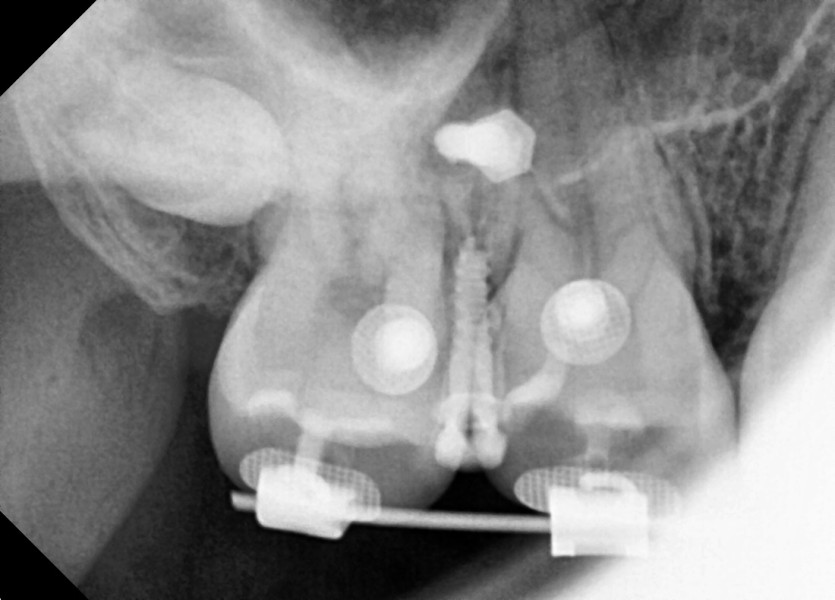

#18 사랑니 발치

구강 외과 전문의가 당일 발치했습니다.